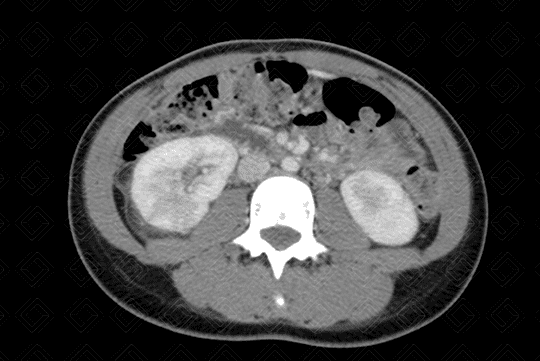

Descrição da lesão: Tomografia computadorizada após a administração do contraste venoso (imagens no plano axial - figuras 1 e 3; e plano coronal - figura 2). Observa-se realce heterogêneo do parênquima renal, com áreas hipocaptantes do meio de contraste venoso (aspecto conhecido como nefrograma estriado).

Há, ainda, lâmina líquida no espaço perirrenal direito (figura 1) e espessamento do urotélio à esquerda (figura 3 - seta vermelha). Estes aspectos são compatíveis com pielonefrite aguda.